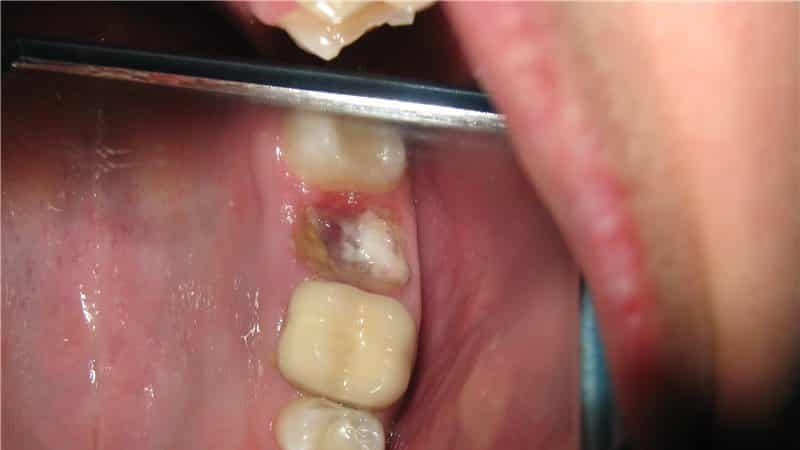

После удаления зуба лунка обычно заполняется сгустком крови, что является нормальным этапом заживления. Иногда этот сгусток может иметь желтоватый оттенок из-за выделения фибрина. Однако, если пациент замечает нагноение в области лунки и выделение жидкости, это может свидетельствовать о воспалительном процессе, известном как «альвеолит».

Со временем защитный сгусток может разрыхляться и размокать под воздействием гноя, что приводит к появлению неприятного запаха изо рта, усилению боли и отека. Внешний вид лунки напоминает рану, заполненную отмершими клетками, остатками пищи и жидкостью с примесями гноя.

Ответственность врача может быть установлена, если в лунке остался фрагмент корня или осколок зубной ткани. Кроме того, неопытный врач может оставить в удаленной области кисту с патогенной микрофлорой, что приведет к нагноению и некрозу тканей.